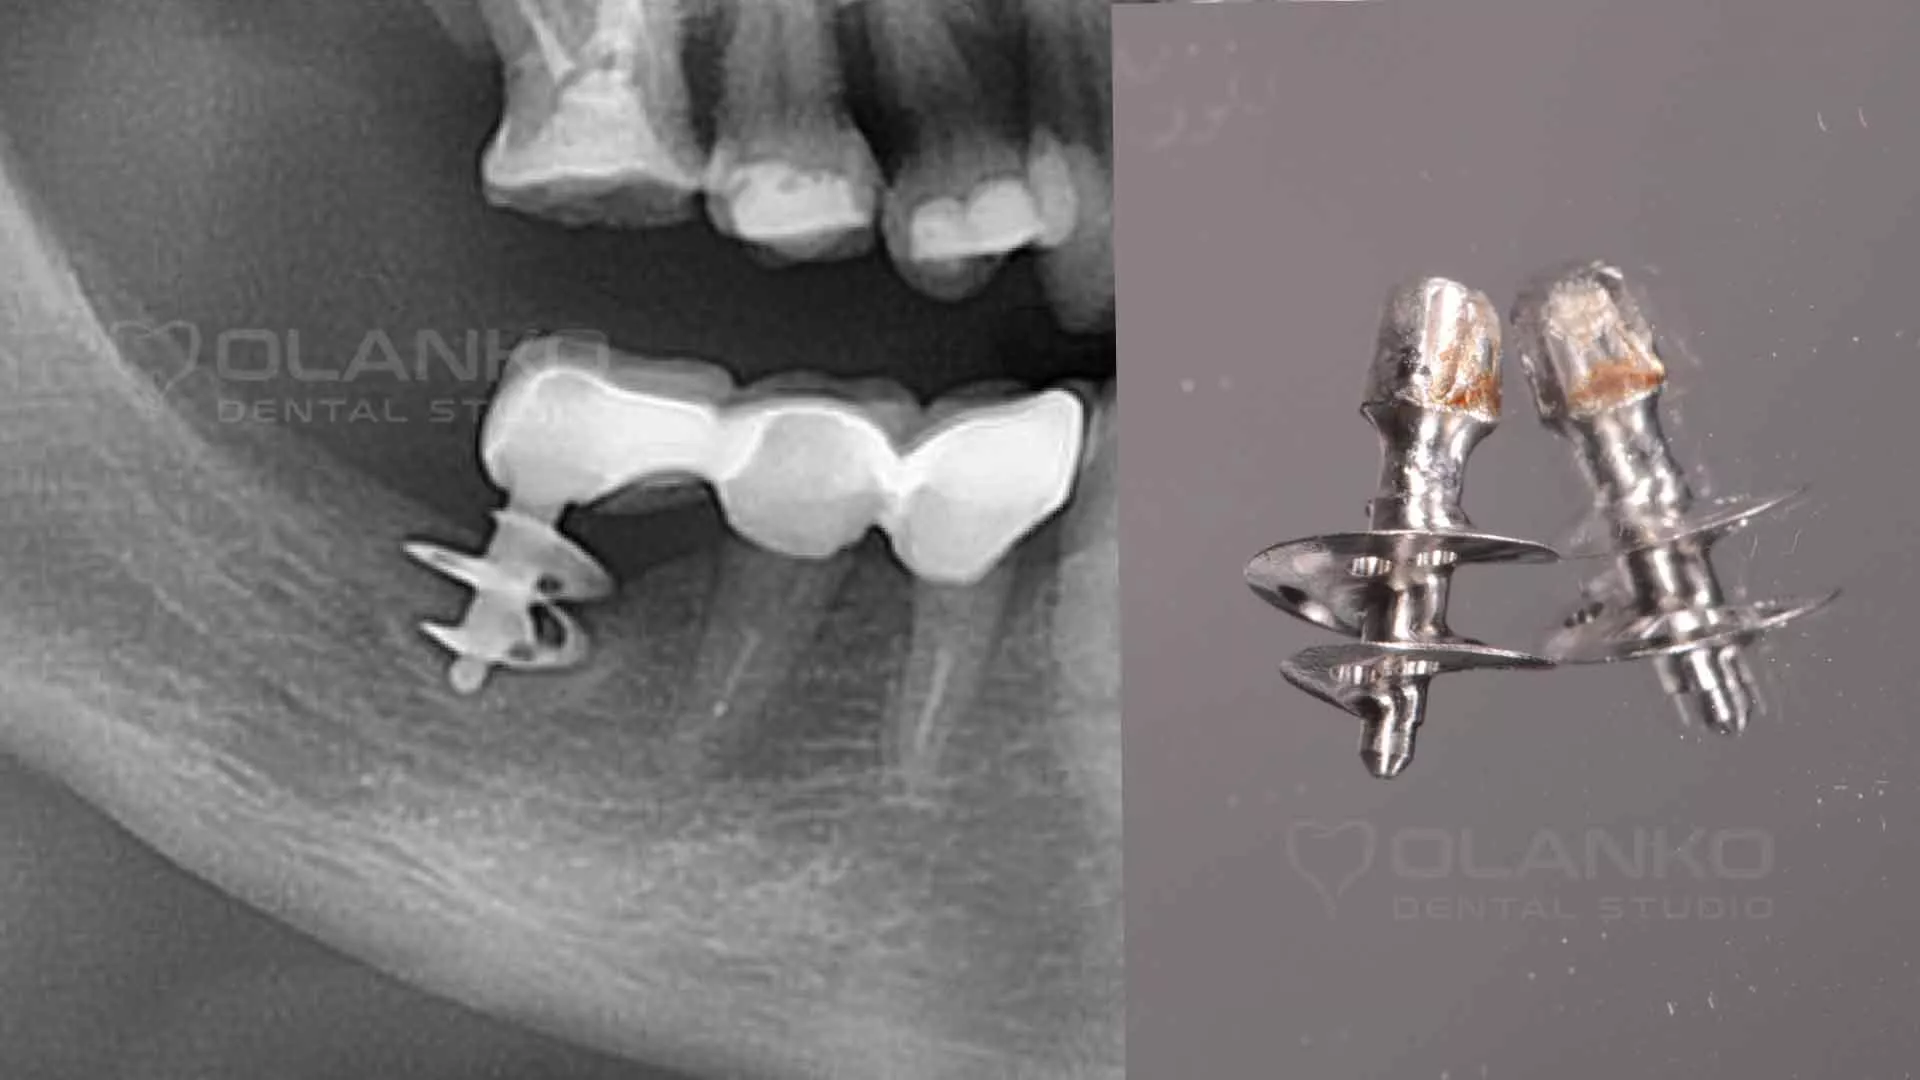

5. На місці відторгнення такого протезу часто виникають великі кісткові дефекти. Численні фото базальної імплантації показують як може статися відторгнення протеза.

Фото приклад видалення базального імплантату внаслідок відторгнення через 2 роки після установки

Базальна імплантація Стоматологія Оланко™